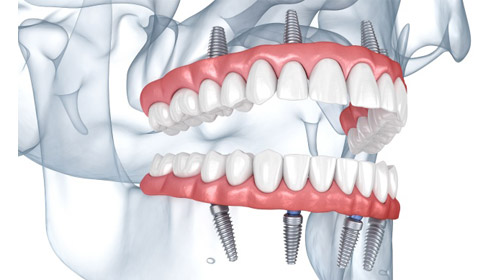

オールオン4と

インプラントの違い

オールオン4

インプラント

骨量や骨質に不安がある方には、6本で支える「オールオン6」という選択肢もあります。

顎の骨がやわらかい方や骨量が限られている方では、6本で分散して支えることで負担を軽減できる場合があります。骨の状態を精密に診断したうえで、より適した方法をご提案します。